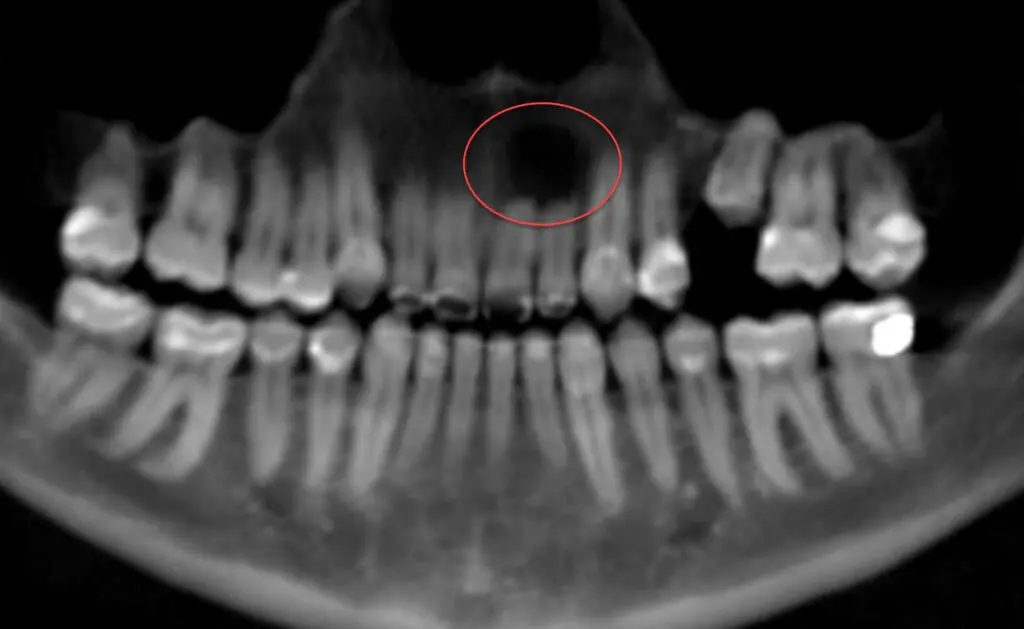

Case 2: Pathology. This patient came in for a routine consultation, and we noticed something that didn’t look right. On the 2D x-ray, the dark spot doesn’t look too significant. But when looking at the case in 3D, you can see a large area of bone is missing due to a long-standing infection that his general dentist hadn’t diagnosed. We were able to refer the patient to another specialist for evaluation and treatment.